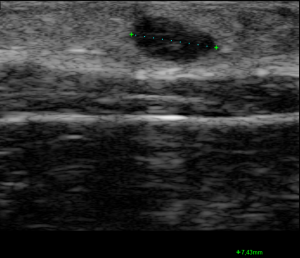

🔹 Caso 1: un pequeño bulto en la piel

Una paciente joven acude preocupada por un pequeño bulto que notó hace un par de días en la parte baja del abdomen. Al explorarlo no dolía, pero se palpaba firme, bien delimitado. ¿Podría ser un ganglio? ¿Un quiste?

La ecografía mostró un quiste epidérmico superficial, bien delimitado, sin signos inflamatorios. Bastó una imagen rápida para tranquilizar a la paciente y evitar pruebas innecesarias.

Recordar por pequeño que es el bulto, debemos palpar bien, para colocar la sonde lineal correctamente, y ajustar los parametros de profundidiad muy superfecial, con la frecuencia al maximo, con centrar el foco y la gancncia. Una vez en el foco adecuado hacer los zum necesarios.